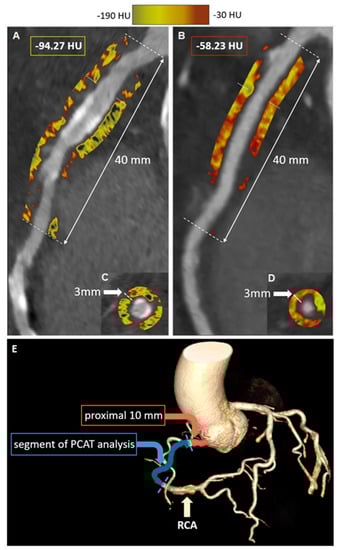

- Kwiecinski, J.; Dey, D.; Cadet, S.; Lee, S.-E.; Otaki, Y.; Huynh, P.T.; Doris, M.K.; Eisenberg, E.; Yun, M.; Jansen, M.A.; et al. Peri-Coronary Adipose Tissue Density Is Associated With 18F-Sodium Fluoride Coronary Uptake in Stable Patients with High-Risk Plaques. JACC Cardiovasc. Imaging 2019, 12, 2000–2010. [Google Scholar] [CrossRef]

- Tzolos, E.; McElhinney, P.; Williams, M.C.; Cadet, S.; Dweck, M.R.; Berman, D.S.; Slomka, P.J.; Newby, D.E.; Dey, D. Repeatability of quantitative pericoronary adipose tissue attenuation and coronary plaque burden from coronary CT angiography. J. Cardiovasc. Comput. Tomogr. 2021, 15, 81–84. [Google Scholar] [CrossRef]

- Van Diemen, P.A.; Bom, M.J.; Driessen, R.S.; Schumacher, S.P.; Everaars, H.; de Winter, R.W.; van de Ven, P.M.; Freiman, M.; Goshen, L.; Heijtel, D.; et al. Prognostic Value of RCA Pericoronary Adipose Tissue CT-Attenuation Beyond High-Risk Plaques, Plaque Volume, and Ischemia. JACC Cardiovasc. Imaging 2021, 14, 1598–1610. [Google Scholar] [CrossRef]

- Tzolos, E.; Williams, M.C.; McElhinney, P.; Lin, A.; Grodecki, K.; Tomasino, G.F.; Cadet, S.; Kwiecinski, J.; Doris, M.; Adamson, P.D.; et al. Pericoronary Adipose Tissue Attenuation, Low-Attenuation Plaque Burden, and 5-Year Risk of Myocardial Infarction. JACC Cardiovasc. Imaging 2022, 15, 1078–1088. [Google Scholar] [CrossRef]